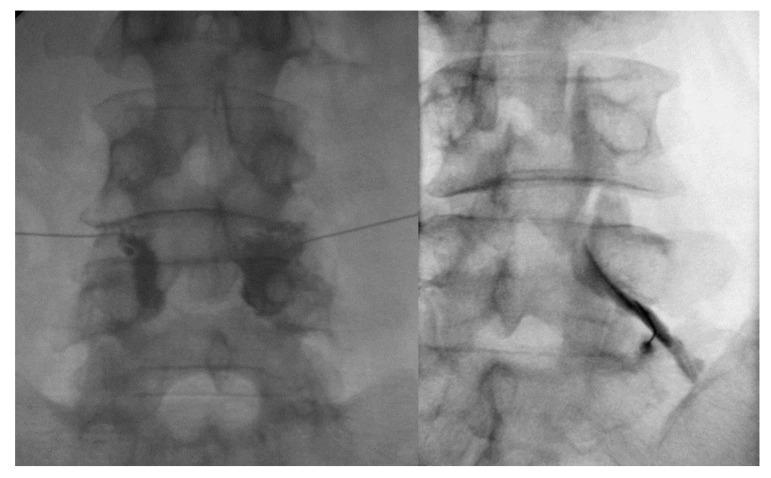

Lumbar central spinal stenosis (LCSS) is a common disorder that causes disability and pain in the elderly. It causes pain in the radicular leg. Recently, transforaminal epidural steroid injection (TFESI) has been widely used to control radicular leg pain caused by LCSS. However, in cases of severe LCSS, drugs injected using TFESI cannot spread into the spinal canal and would have less therapeutic effects than in mild LCSS. To compensate for this limitation of TFESI, we injected steroids and botulinum toxin type A into the bilateral facet joints, evaluated their effects, and compared them with those of TFESI. One hundred patients with severe LCSS were included in the study and randomly allocated to either the facet injection (FI) or TFESI group. For 50 patients in the FI group, 30 mg (40 mg/mL) of triamcinolone with 50 IU of botulinum toxin type A mixed with a 1 mL solution of 100 mL of 50% dextrose water and 30 mL of 4% lidocaine were administered into the bilateral facet joints under fluoroscopy. For 50 patients in the TFESI group, 30 mg (40 mg/mL) of triamcinolone with 0.8 mL of 2% lidocaine and 2.5 mL of 50% dextrose water was injected bilaterally under fluoroscopy. Radicular leg pain (measured with a numeric rating scale) and pain-related disability (measured with the modified Oswestry Disability Index) due to severe LCSS were significantly reduced after facet joint injection. The therapeutic effects were greater after facet joint injection than after bilateral TFESI. The injection of a mixed solution of steroids and botulinum toxin type A into the bilateral facet joints would be a beneficial therapeutic option in patients with severe LCSS.

腰椎中央椎管狭窄症(LCSS)是一种常见疾病,会导致老年人出现残疾和腰痛。它会引起神经根性腿痛。最近,经椎间孔硬膜外类固醇注射(TFESI)已广泛用于控制 LCSS 引起的神经根性腿痛。然而,在严重 LCSS 的情况下,使用 TFESI 注射的药物无法扩散到椎管内,其治疗效果不如轻度 LCSS。为了弥补 TFESI 的局限性,我们将类固醇和肉毒毒素 A 注射到双侧关节突关节内,评估其效果,并将其与 TFESI 进行比较。本研究纳入了 100 例严重 LCSS 患者,并随机分为关节突关节内注射(FI)或 TFESI 组。FI 组的 50 例患者,在透视下向双侧关节突关节内注射 30mg(40mg/mL)曲安奈德,混合 50IU 肉毒毒素 A,再用 100mL 50%葡萄糖水和 30mL 4%利多卡因稀释至 1mL。TFESI 组的 50 例患者,在透视下向双侧关节突关节内注射 30mg(40mg/mL)曲安奈德,混合 0.8mL2%利多卡因和 2.5mL50%葡萄糖水。严重 LCSS 引起的神经根性腿痛(用数字评分量表测量)和与疼痛相关的残疾(用改良 Oswestry 残疾指数测量)在关节突关节内注射后显著减轻。关节突关节内注射的疗效大于双侧 TFESI。在严重 LCSS 患者中,将类固醇和肉毒毒素 A 的混合溶液注射到双侧关节突关节内可能是一种有益的治疗选择。